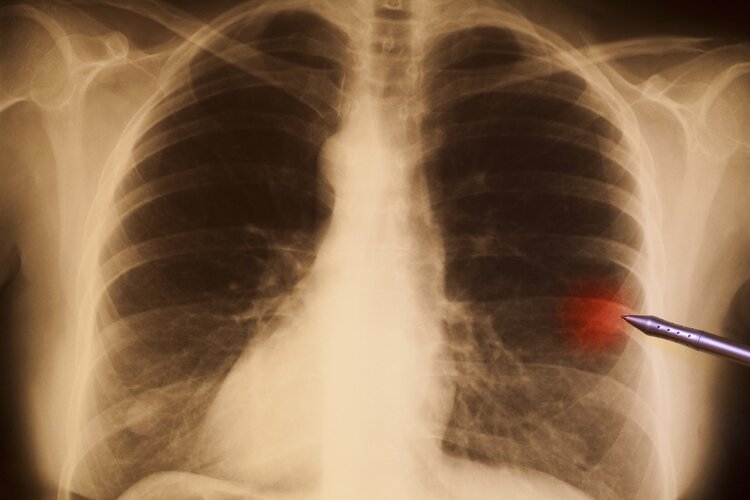

江女士本来没放在心上,但是听家里人这么说也有道理,于是第二天就去往了当地的医院进行检查。当时接诊吴女士的医生,对于杵状指有所了解,一看到江女士就建议她去做个肺部CT,怀疑是肺癌所致。

在医生详细解释下,吴女士还是听从了医生的建议进行了肺部CT检查。

检查结果出来后,果然如医生所料,吴女士肺部内有一个3cm左右的肿瘤,医生判断为早中期肿瘤,建议立即住院进行手术。

直到上了手术台,江女士还是没缓过神来,自己不过就是检查个手指头,怎么就肺癌了呢?